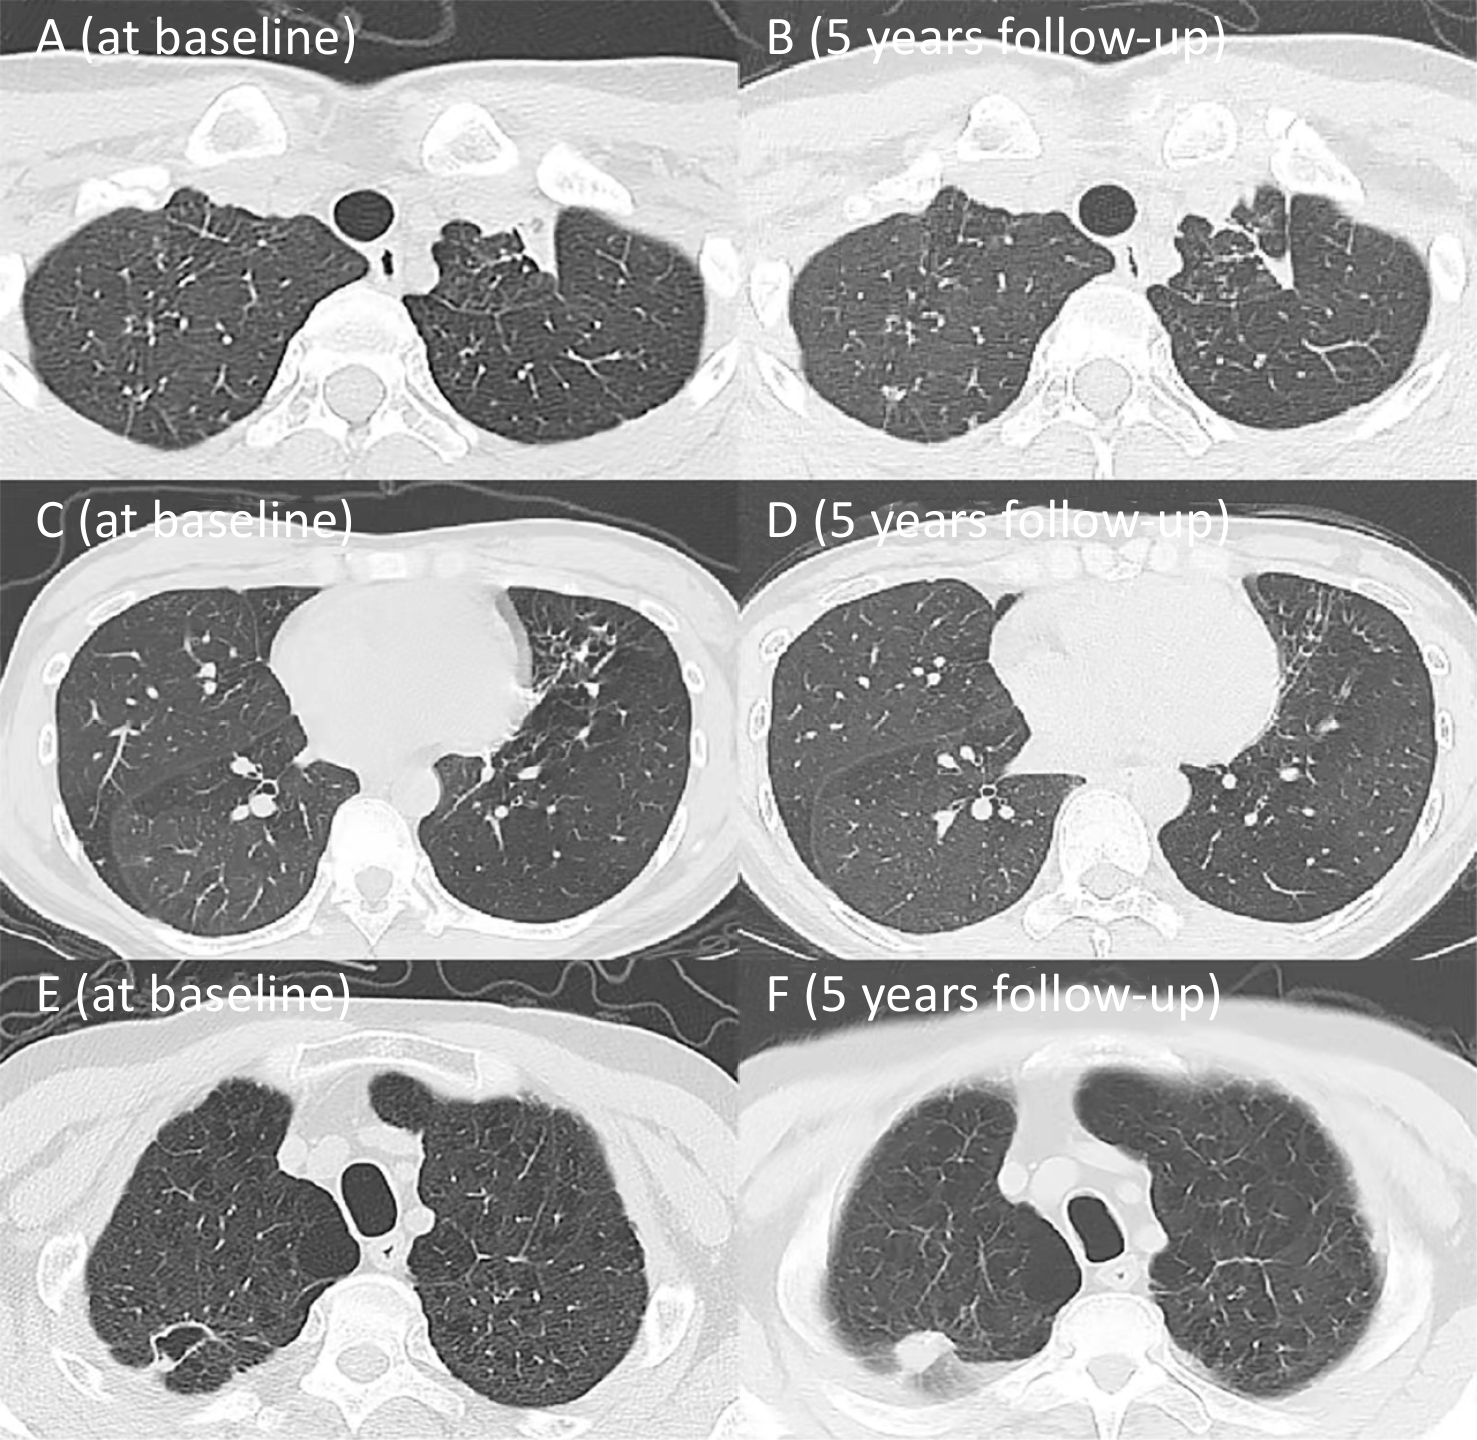

Airflow Obstruction in Post-tuberculosis Lung Disease: A 5-year Prospective Cohort Study

Zikang Sheng, Wenli Cao, Hongling Chu, Yanqing Le, Junfeng Wu, Yue Zhang, Yafei Rao, Brian Allwood, Yongchang Sun, Xiaoyan Gai

2026, 39(2): 146-157. doi: 10.3967/bes2025.121

Objective   Post tuberculosis lung disease (PTLD) manifests in various forms, including tuberculosis-associated chronic obstructive pulmonary disease (TB-COPD), yet the clinical features of PTLD remain undercharacterized. This study aimed to assess longitudinal changes in lung function over a 5-year period and to identify predictors of airflow obstruction in a cohort of patients treated for active pulmonary TB.  Methods   Patients with active pulmonary TB were enrolled in this study and were followed during treatment, at treatment completion and five years post-treatment. Assessments included lung function and chest CT, analyzing longitudinal trends and airflow obstruction risk factors.  Results   Among 53 patients (mean age 36.9 ± 13.9 years; 64.2% male), 7 patients (13.2%) exhibited airflow obstruction. At the 5-year follow-up, the mean FEV1/FVC declined significantly (76.27% ± 12.04% vs. 80.23% ± 11.02%, P < 0.001) and 9 patients (17.0%) exhibited airflow obstruction. Seven of these patients predominantly showed air trapping consistent with small airway disease on chest CT, aligning with TB-COPD phenotype. Notably, four young-to-middle-aged patients (< 60 years old) had persistent obstruction over the five years.  Conclusion   The initial test revealed that 13.2% of patients presented with airflow obstruction. By the 5-year follow-up, this proportion had increased to 17.0%, with most cases demonstrating imaging findings aligning with TB-COPD, even among younger, non-smoking individuals. These findings emphasize the importance of long-term follow-up and routine lung function assessments in TB survivors.